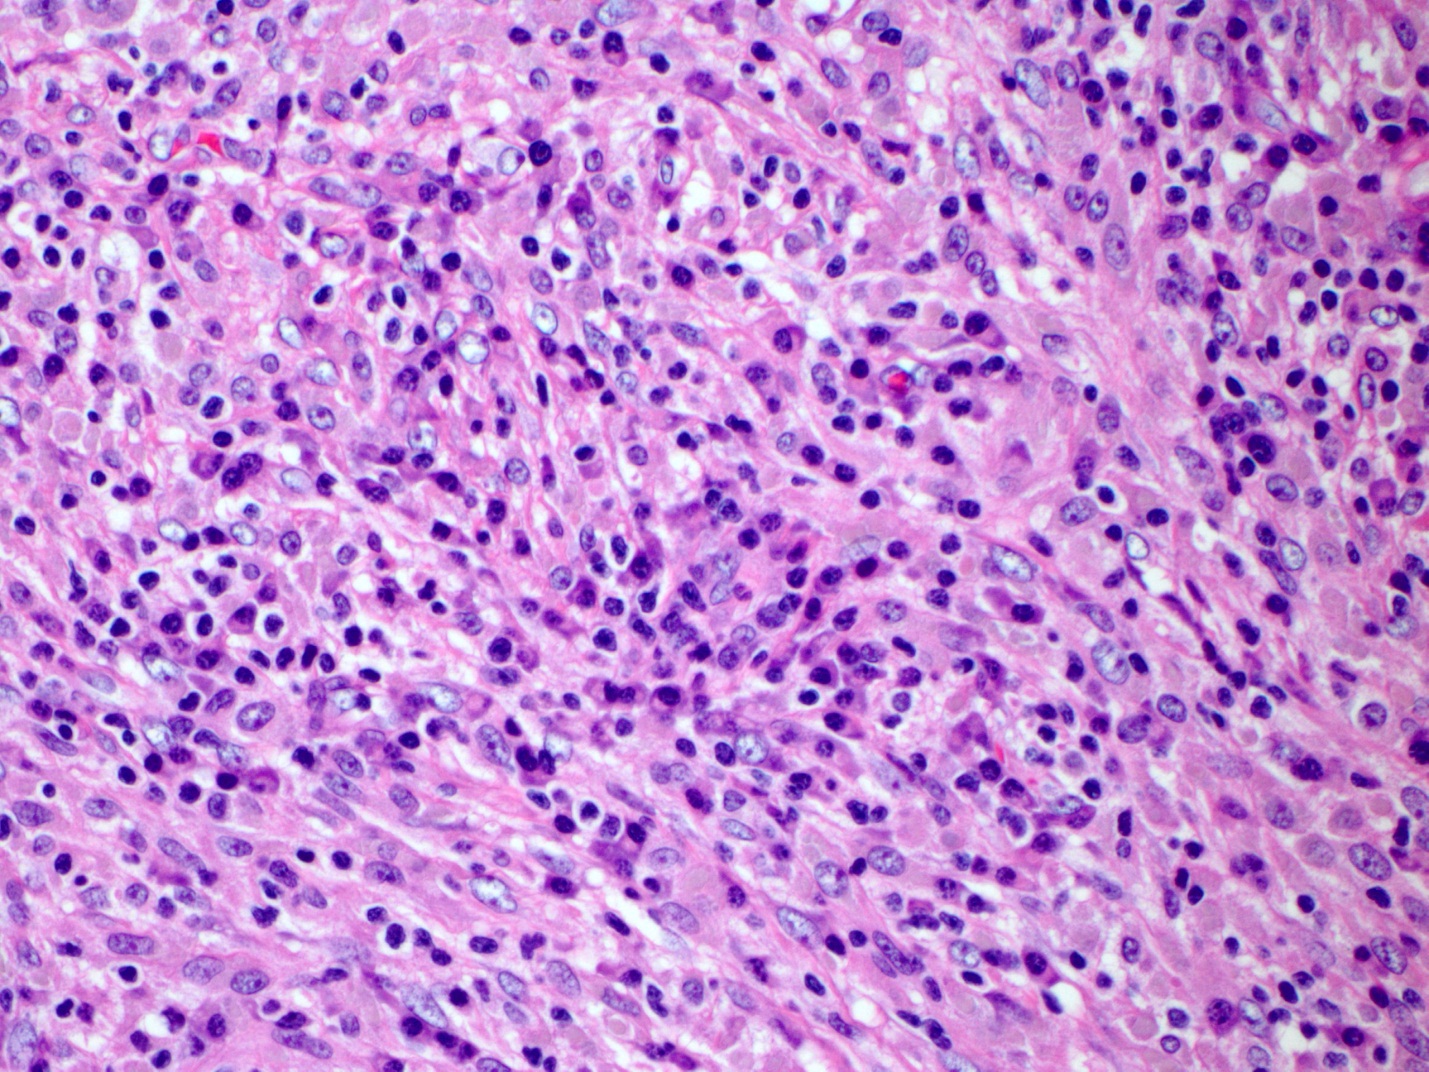

Sections of the gallbladder demonstrated a marked chronic inflammatory infiltrate with numerous germinal centers and plasma cells involving the lamina propria and muscularis mucosa, with focal involvement of the submucosa (Figures 1&2). The submucosa was fibrotic. Immunohistochemistry demonstrated polytypic plasma cells with clusters of up to 40 IgG4 positive plasma cells per 40x field (Figure 3). The superficial gallbladder wall demonstrated scattered IgG4 plasma cells and the deeper, more fibrotic portions of the gallbladder wall demonstrated prominent clusters of IgG4 positive plasma cells. The surface epithelium showed mild reactive changes but no dysplasia. Sections of the liver segmentectomy showed normal architecture. Portal areas contained mild to moderate chronic inflammatory infiltrates. A few portal areas demonstrated prominent clusters of lymphocytes. Many portal areas did not contain a portal vein branch and in one septal portal area there was fibrous obliteration of the vein (Figure 4, white arrow). The parenchyma demonstrated atrophy of zone 3 hepatocytes (blue arrow) compatible with portal vein compromise (Figure 5).

| Figure 2 |